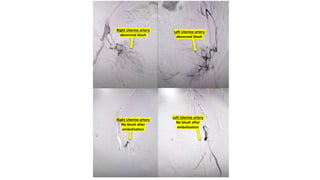

The document details a series of vascular procedures, including recanalization of the peroneal artery, medial plantar artery, and right brachiocephalic vein following occlusions. It also mentions angioplasty and the presence of abnormal blood flow in various uterine and bronchial arteries, along with complications like CBD obstruction due to a periampullary adenocarcinoma. Additional notes on venous collaterals and their disappearance are included.